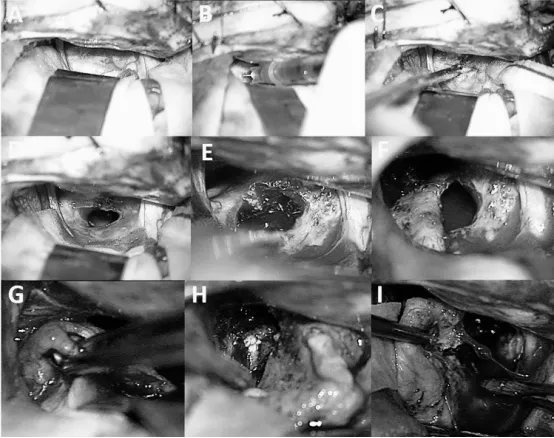

同一病例术中视图(该患儿于8岁时接受手术,即腔内治疗3年后因肿瘤初步再生而进行)。尽管已抽吸囊液(A、B、C),肿瘤包膜仍呈现纤维化、增厚,且与周围结构粘连紧密难以分离;囊液移除后包膜未见塌陷(D、E、F)。这种情况使肿瘤切除手术更为复杂(G、H、I)。